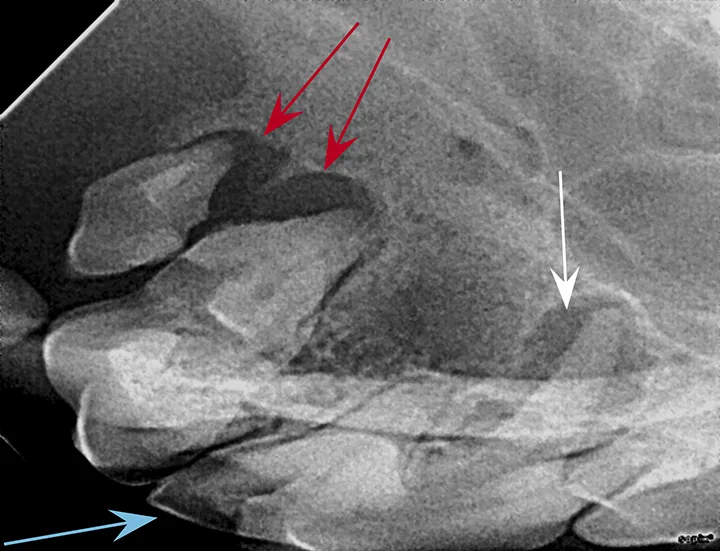

Periapical lucency develops secondary to bone loss around the tooth root caused by endodontic, neoplastic, or periodontal disease. In this dog, periapical lucency of the maxillary first and second molars (red arrows) developed secondary to periodontal disease. Periapical lucency secondary to endodontic disease (caused by exposure of the pulp from a slab fracture [blue arrow]) is also present surrounding the roots of the right maxillary fourth premolar (white arrow).

Observation of marked mobility of the molars would be expected on anesthetized examination. In this dog, the maxillary fourth premolar would likely not be mobile, as there is still bone surrounding the root apices. Extraction of the maxillary fourth premolar and first and second molars is indicated.